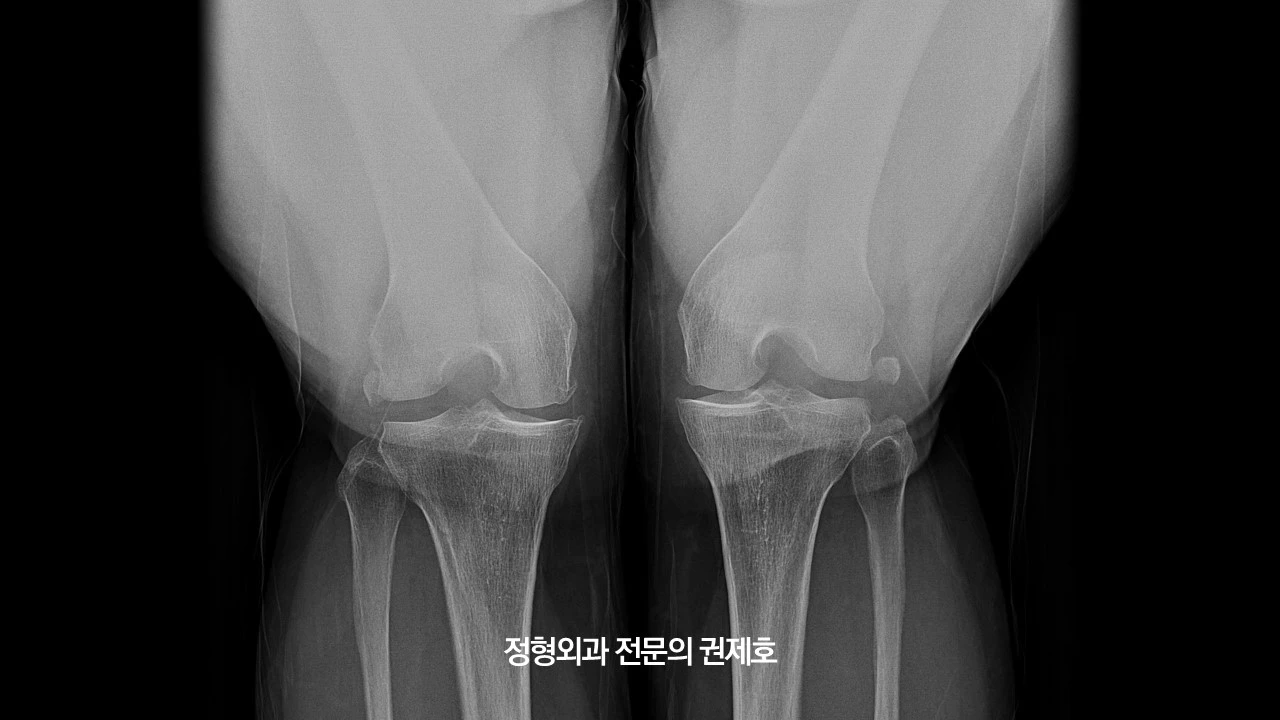

무릎이 아파서 병원에 와보신 분들은 아시겠지만, 보통 여러 장의 사진을 찍지만 중요한 사지만 추렸습니다. 맨 위 사진은 서서 앞에서 촬영한 것이고 그다음 사진은 뒤에서 구부린 상태로 촬영한 로젠버그 사진입니다. 둘 다 보면 관절염이 아주 심해 보이진 않지만, 관절 간격이 좁아진 것이 관찰되고 있습니다.

제가 가장 중요하게 여기는 하지 정렬 검사 사진입니다. 보시면 무릎이 많이 휘어 있는 것을 아실 수 있습니다. 바로 오다리입니다. 아마도 어릴 적부터 원래 오다리였다고 사료되며, 관절염으로 진단받고 관리는 하였으나 아마도 기존에 있던 휜다리가 증상 악화의 요인이 아닐까 생각하며, 비교적 젊은 나이이고, 다른 이상 소견이 있는지 확인하기 위해 MRI 검사를 진행했습니다.